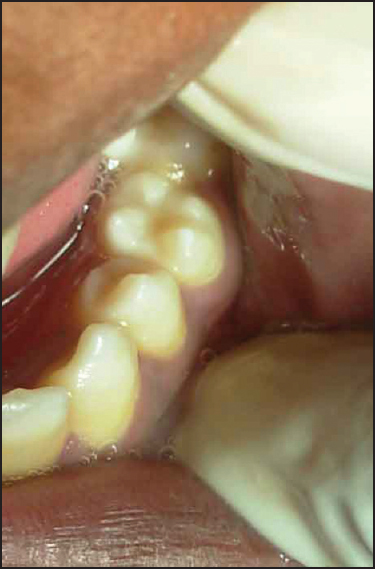

Figure 2: Photograph showing the mandibular second left premolar with four cusps looking like a molar (molarized premolar)